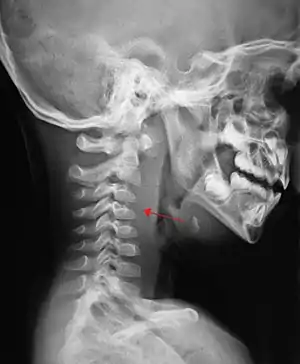

| A lateral neck X-ray demonstrating soft tissue swelling in front of the vertebrae (marked by the arrow) as seen in a person with a retropharyngeal abscess. | |

X-ray of the neck 80% of the time shows swelling of the retropharyngeal space in affected individuals. If the retropharyngeal space is more than half of the size of the C2 vertebra, it may indicate retropharyngeal abscess.[7]